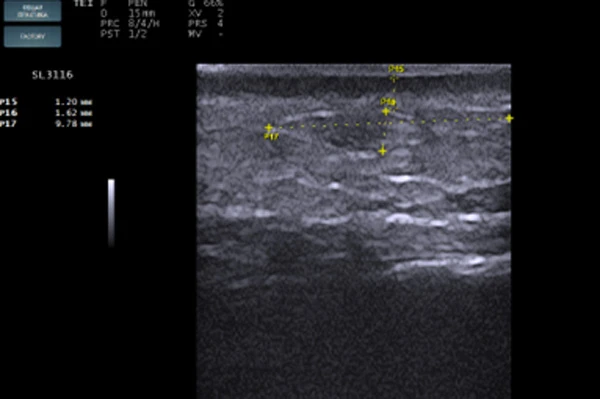

STYLAGE® HydroMax был введен в область губ и периоральной зоны комплектной иглой 30 G в линейно-ретроградной (мезоармирующей) технике. Слой введения — глубокая дерма (Рис. 1). Сразу после введения была выполнена сонограмма в зоне носогубной складки (Рис. 2). На изображении хорошо видны зоны имплантата анэхогенной структуры с ровными краями, овоидной формы, так же заметно, что ткани в этой области сдвинуты по направлению друг от друга и между дермой и мышечным слоем определяется наличие геля. На контрольной сонограмме, сделанной через 4 месяца (Рис. 3), имплант приобретает изоэхогенную структуру, в нем определяются гипоэхогенные включения, что указывает на начало процесса биодеградации и замещение импланта собственными тканями. На сонограмме 3, выполненной через 13 месяцев (Рис. 4), хорошо визуализируется участок локации импланта с границей гиперэхогенной капсулы, внутри которой определяется полное разрешение процесса биодеградации.

Сонограмма дермального имплантата

Рис. 3. Сонограмма дермального имплантата через 4 месяца после введения